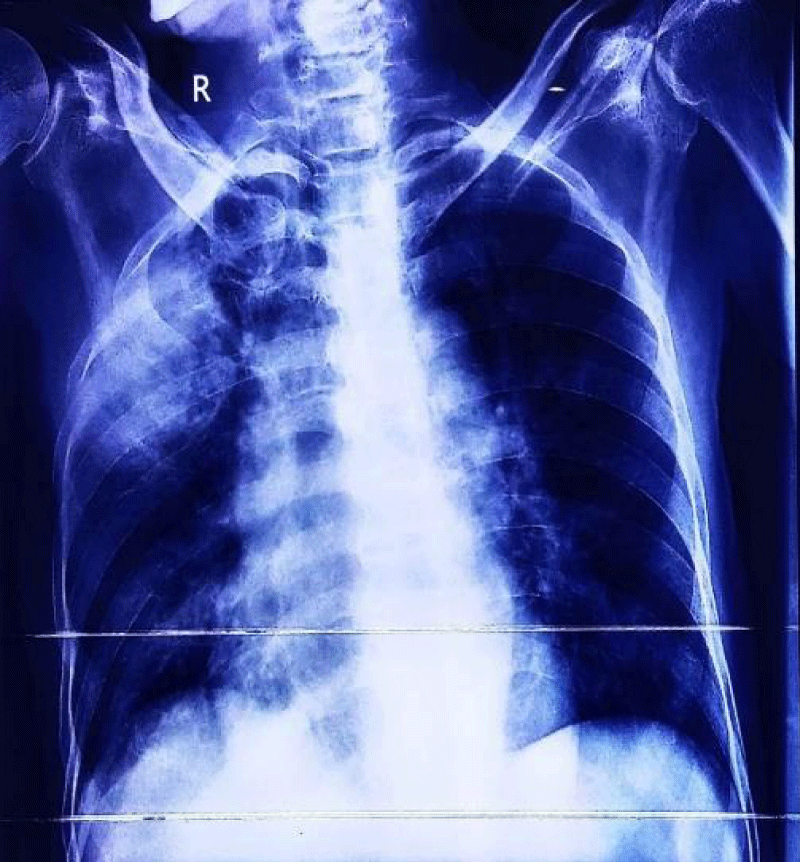

A 33-year-old industrial worker hailing from rural Bangladesh presented with sudden onset of inability to swallow both solid and liquids, voice change for 6 days, fever and worsening cough with expectoration of sputum for 3 days. Fever was high grade, intermittent. Highest recorded temperature was 103˚F. He denied any headache, altered sensorium, convulsion, shortness of breath, hemoptysis, chest pain, any limb weakness or any sphincteric or sensory disturbances. On query there was nasal regurgitation of food materials. On general examination he was febrile with pulse 102 beats/min, regular, BP 100/60 mm of Hg, respiratory rate 16 breaths/min. Chest examination revealed bronchial breathing with increased vocal resonance over right upper chest. Neurological examination revealed patient was conscious, oriented with right sided palatal palsy with absent gag reflex and hoarse voice, reduced muscle power over right trapezius and right sternocleidomastoid muscle with lateral winging of right scapula (Figure 1). Rest of other neurological examination revealed no abnormalities. On past history, he had road traffic accident three months back and hospitalized in intensive care unit at Malaysia for 1 month with the diagnosis of severe traumatic brain injury with left temporal and cerebellar extradural hematoma, with multiple facial and skull bone fracture and upper GI bleed from stress ulcer. He underwent bifrontal decompressive craniectomy. Initial investigation revealed, neutrophilic leukocytosis with total count 17,800/cmm with neutrophil 82%, ESR was 113 mm in 1st hour, CRP was 237 mg/dl. Liver function tests, renal function tests and MRI brain revealed no abnormalities. Chest X ray showed consolidation over right upper chest (Figure 2).

Figure 2: Showing consolidation over right upper lung.